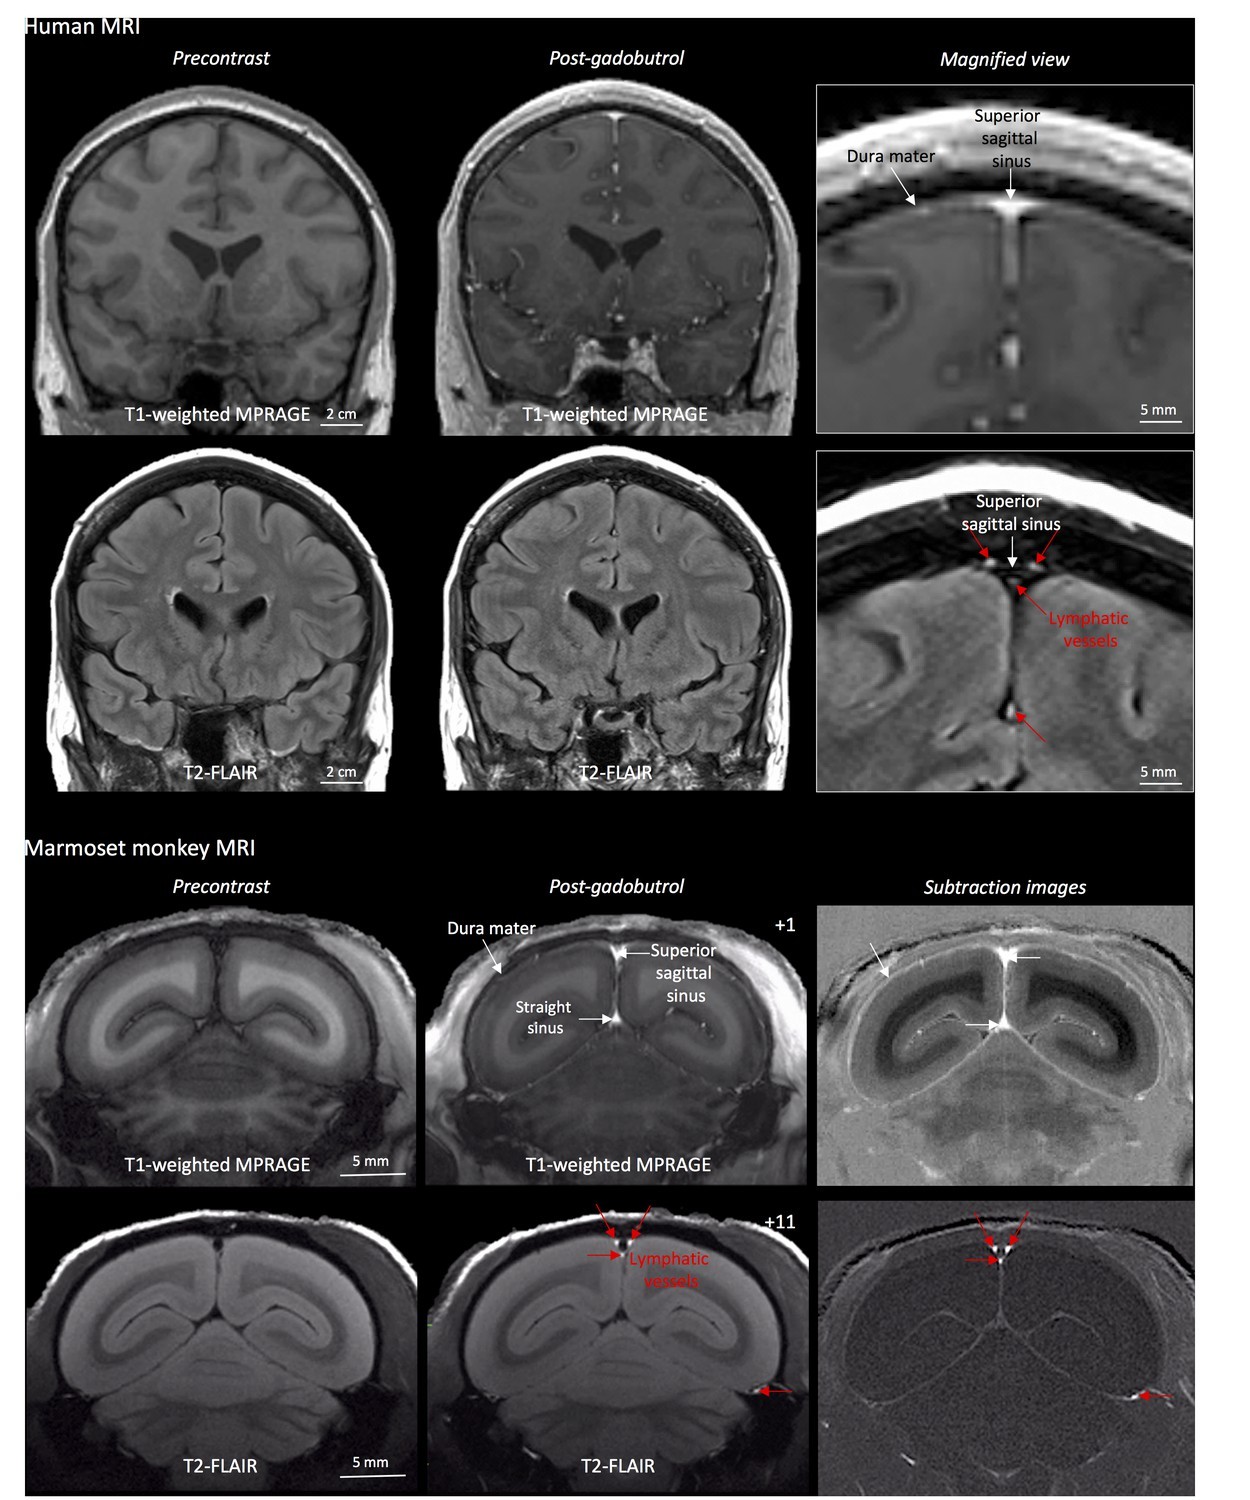

Учёные из Национального института неврологических расстройств и инсульта в США доказали, что мозг человека имеет специальный механизм регулирования и "сливает" патогены и молекулярные отходы через собственный "трубопровод". Учёные выяснили, что смешанные межклеточная и спинномозговая жидкости очищаются с помощью небольшой лимфатической системы. Первоначальное обследование добровольцев с помощью МРТ и введения гадобутрола не показало ничего необычного. Однако после перенастройки оборудования учёные заметили крошечные, едва различимые лимфатические сосуды, через которые мозговой "мусор" выводится в лимфатическую систему.

Исследователи отмечают, что в текущие дискуссии о точной локализации лимфатических сосудов внутри головного мозга можно внести некоторую ясность. Применение МРТ с диффузным усилением даёт основания утверждать, что большая часть лимфатических сосудов находится внутри твёрдой оболочки головного мозга. Детальное изучение результатов МРТ позволило узнать и точную структуру "мозговой канализации" — она состоит из 93 дуральных лимфатических сосудов.